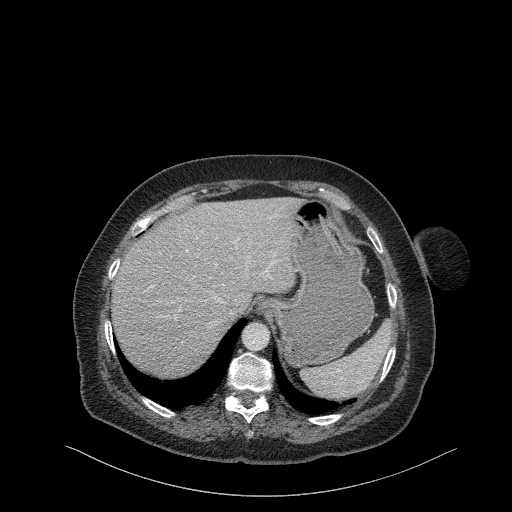

Original VENOUS CT scan

Full window (WL 1023.5, WW 4095 β†’ Low βˆ’1024, High +3071)

Lung window (WL -600, WW 1500 β†’ Low βˆ’1350, High +150)

Mediastinum window (WL 40, WW 400 β†’ Low βˆ’160, High +240)